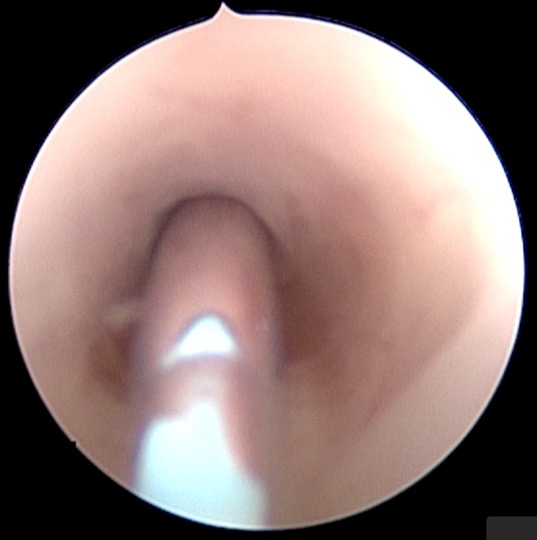

l’endoscopie est un traitement séduisant car elle est peu invasive, et elle suffit souvent à traiter le kyste ; il existe cependant un taux de complication non nul et un taux d’échec qui peuvent rendre nécessaire une autre intervention, shunt ou craniotomie. pour certains kystes comme le kyste supra-sellaire, c’est le traitement de référence ; pour d’autres, c’est un des choix chirurgicaux possibles.

visionner l’endoscopie pour kyste arachnoïdien sylvien

visionner l’endoscopie pour kyste arachnoïdien supra-sellaire

visionner l’endoscopie pour kyste de l’incisure tentorielle